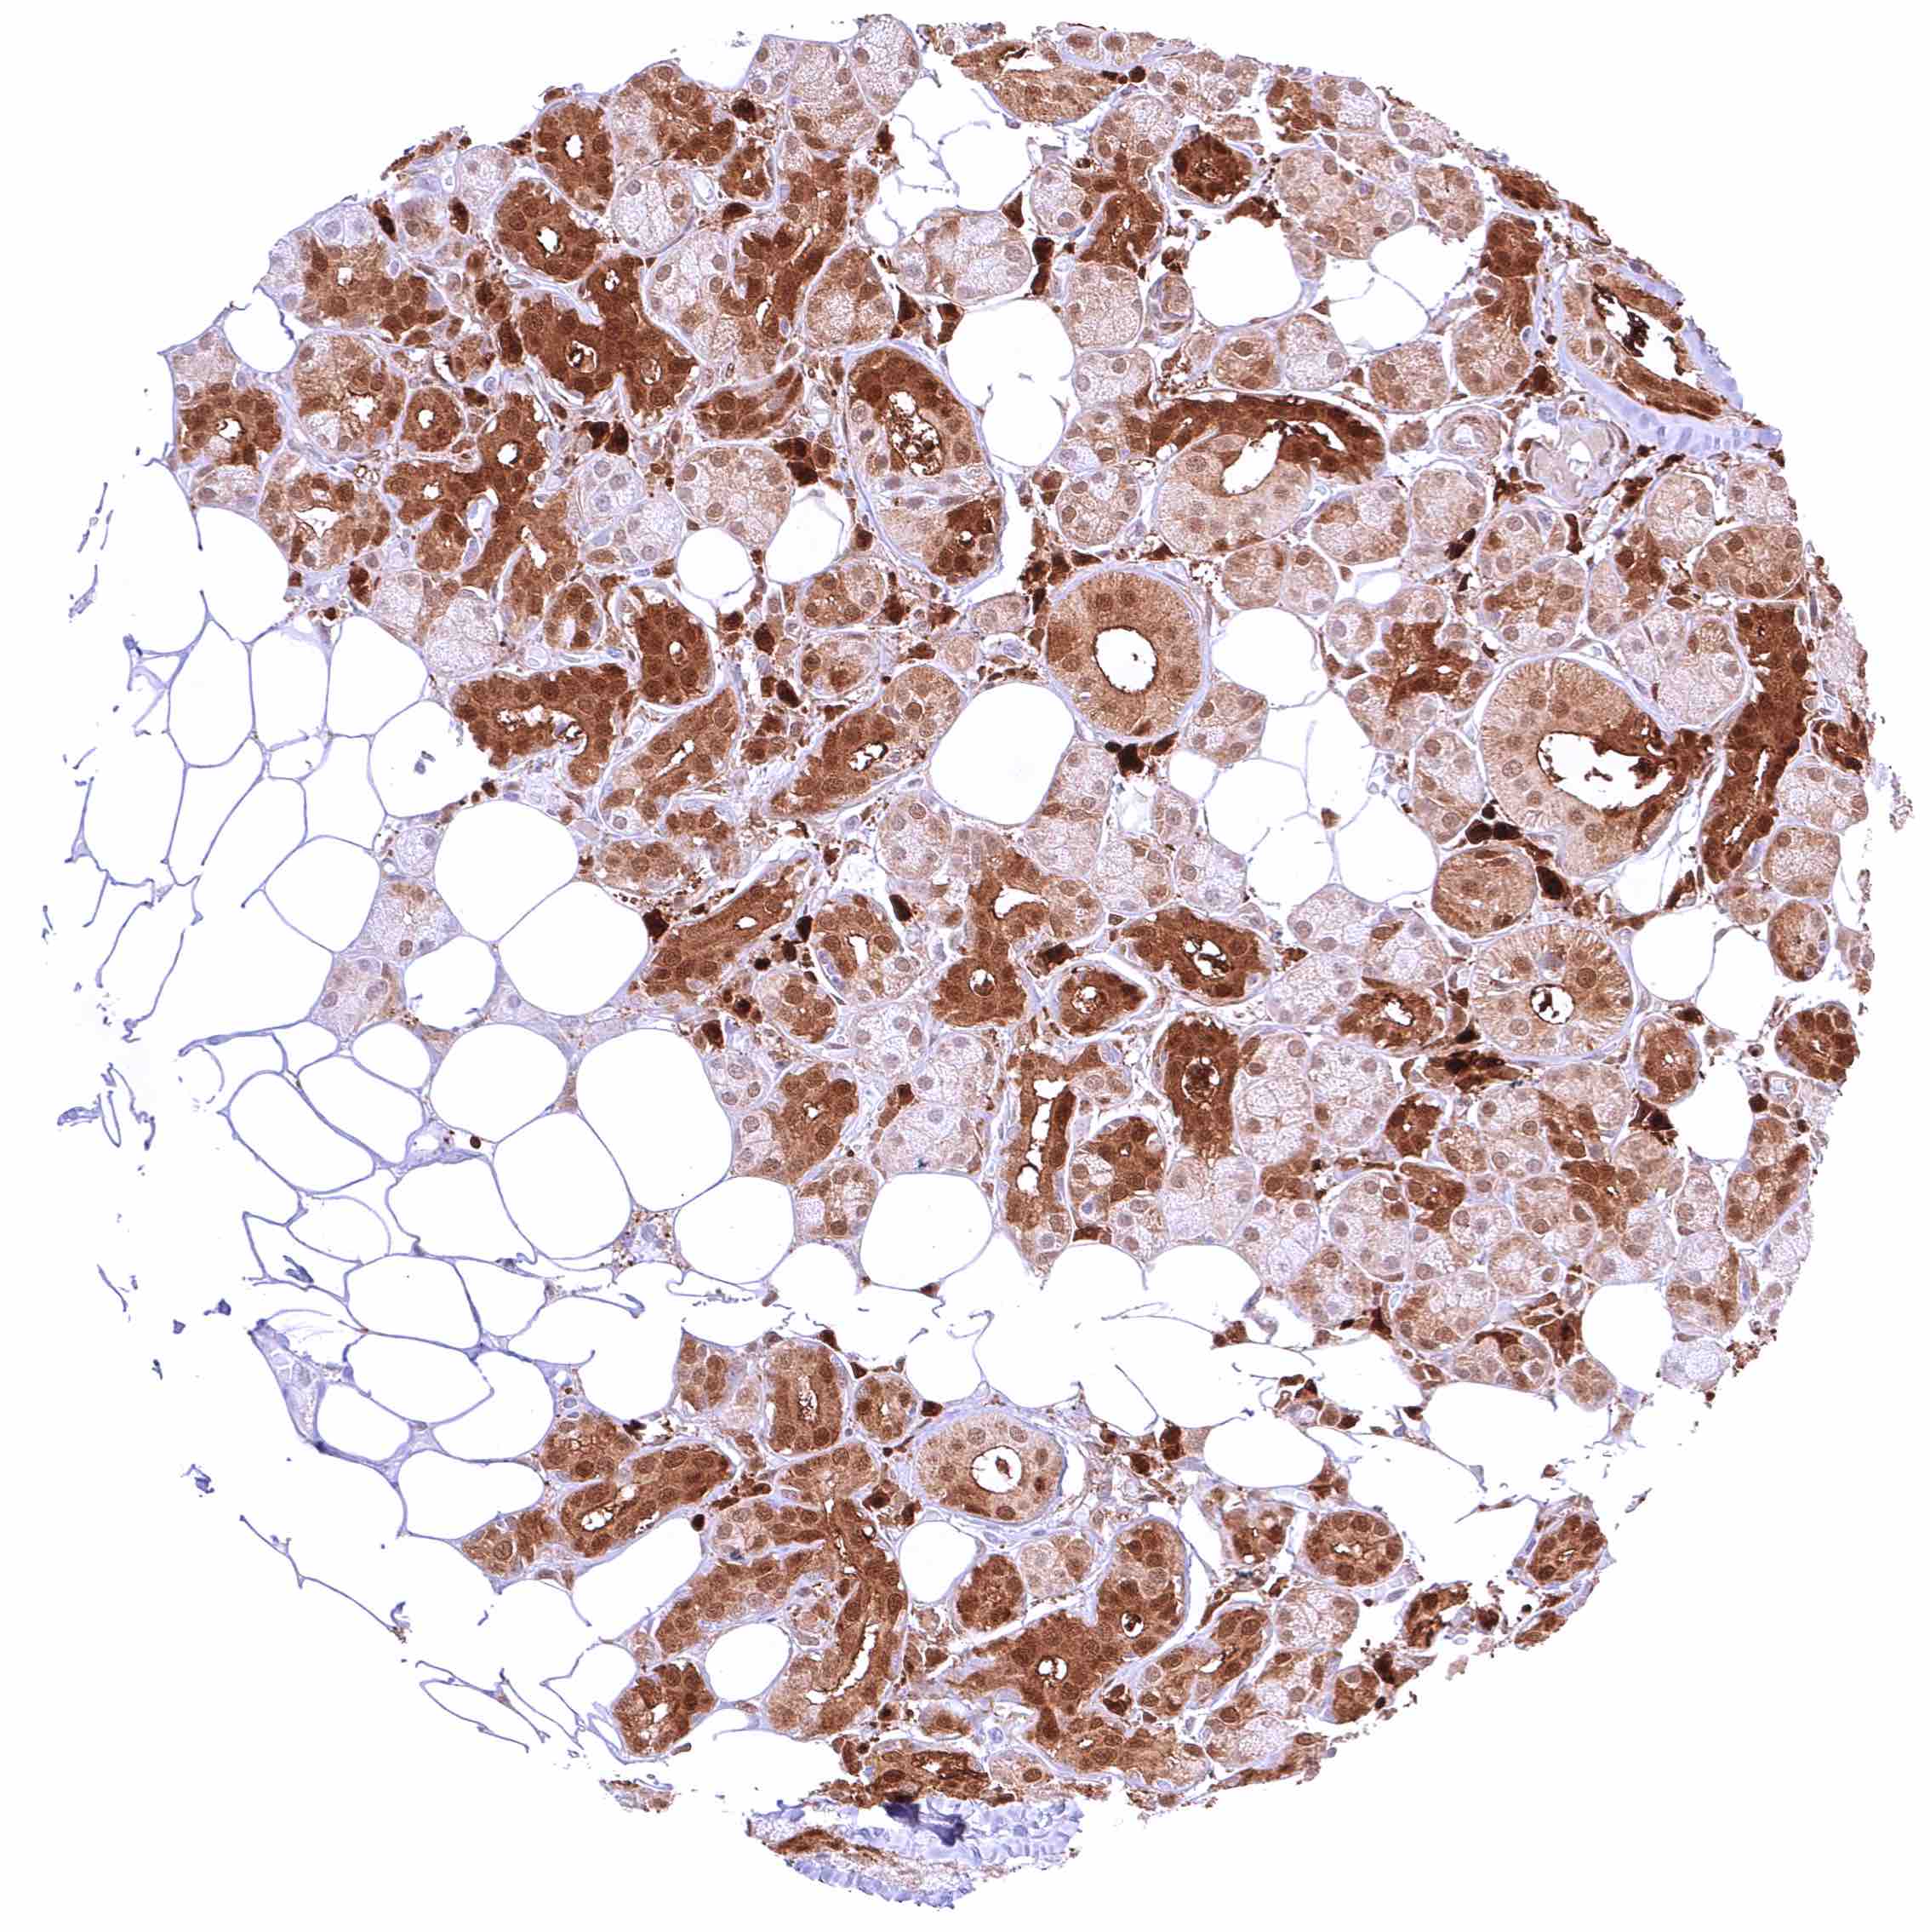

Thyroid gland – Strong nuclear and cytoplasmic GSTP1 positivity of epithelial cells.